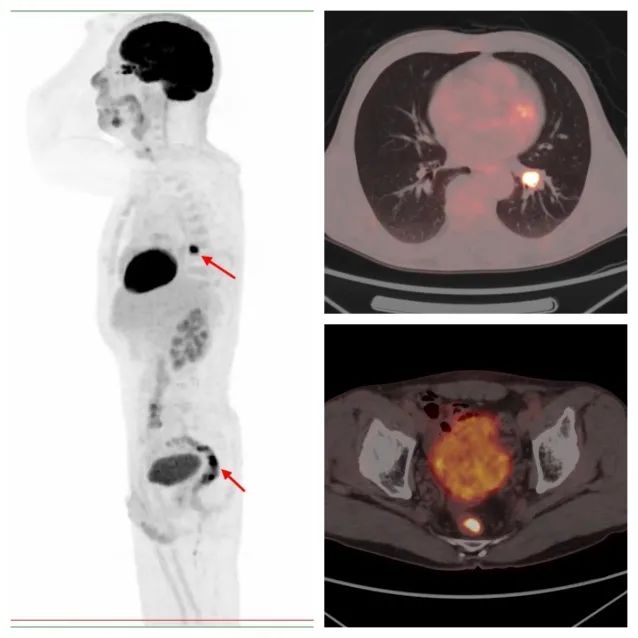

病例2,PET/CT示左肺下叶、直肠代谢异常,符合双原发癌;之后患者行支气管镜下活检,病理证实原发肺鳞癌;行肠镜下活检,病理证实为原发直肠溃疡型腺癌。